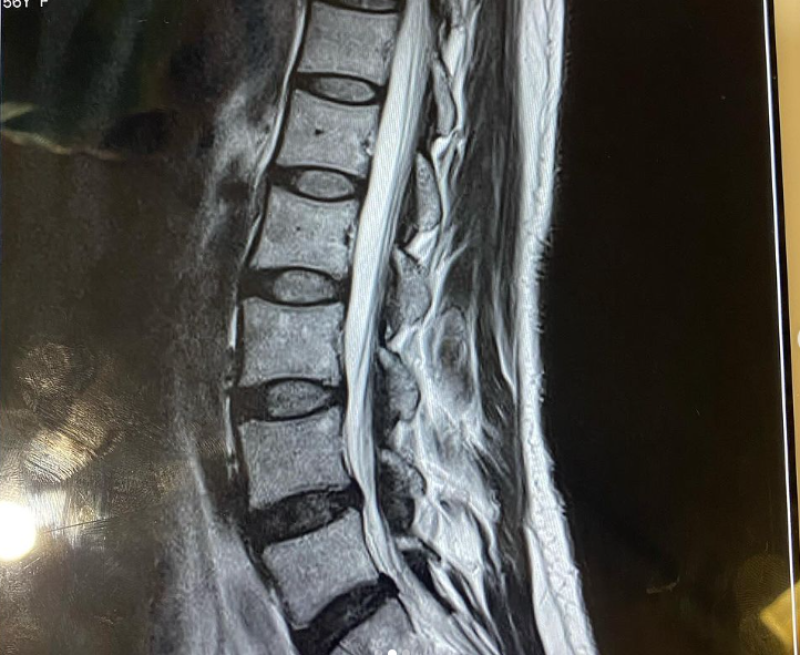

ล่าสุด กวาง กมลชนก ได้ออกมาเผยอาการว่า ขอบพระคุณทุกท่านที่ส่งความห่วงใยมาให้กวางนะคะ กวางมีอาการปวดขามานานแล้วค่ะ(แต่ทน) ช่วงหลังมีปวดหลังและมีอาการชาเพิ่มขึ้นมา และบางวันปวดมากๆจนนอนไม่หลับเลย…..คราวนี้ทำx-rayและMRIพบว่าเป็นหมอนรองกระดูกสันหลังกดทับเส้นประสาทค่ะ แต่ยังเป็นไม่มากจนถึงขั้นต้องผ่าตัดนะคะ คุณหมอรักษาด้วยวิธีประคับประคองอาการไม่ให้เป็นมากขึ้น(จะได้ไม่ต้องผ่าตัด) และดูแลกระดูกที่ยังดีอยู่ให้แข็งแรงต่อไปหลังจากนี้คือต้องทำกายภาพบำบัด สร้างกล้ามเนื้อและต้องมียาประจำเพิ่มขึ้นมาอีก แต่ไม่ต้องห่วงนะคะเพราะเวลานี้ได้กลับบ้านแล้วค่ะ และต้องใช้ชีวิตแบบระวังมากขึ้น